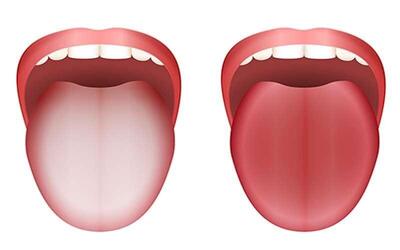

آیا استرس بر سلامت دهان و دندان تاثیر دارد؟ ؛ چه کار کنیم ؟

مطالعات متعدد نشان میدهد که بین استرس و شیوع یا شدت بیماریهای دهان ارتباط آماری وجود دارد. نتایج تحقیقات حاکی از آن است که افراد با سطح استرس بالا، بیشتر به بیماریهای پیشرفته لثه «پریودنتیت پیشرفته» دچار میشوند.